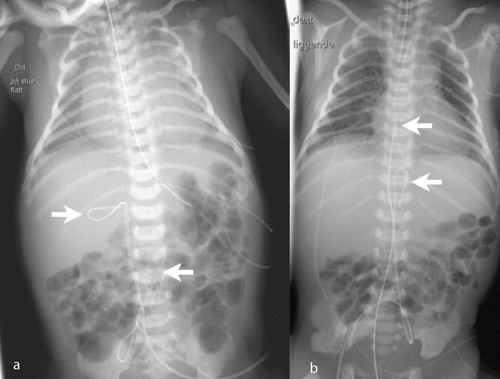

278 navlevenekatetre og 99 navlearteriekatetre ble innlagt hos totalt 298 nyfødte. 78 (26 %) fikk både arterie- og venekateter. Figur 1 – 3 viser røntgenbilder med ulike kateterposisjoner. I ett tilfelle fikk pasienten utilsiktet to navlevenekatetre (fig 2a) og i to tilfeller fant begge katetrene veien til samme navlearterie (fig 2b og 2c). Indikasjonene for innleggelse var prematuritet hos 156 (52 %), asfyksi hos 41 (14 %), infeksjon hos 37 (12 %), respirasjonsbesvær hos 24 (8 %), misdannelser hos 12 (4 %) og andre indikasjoner hos 28 (9 %).

Tabell 1 angir kateterposisjonene. Av navlearteriekatetrene var 45/99 (45 %) primært riktig plassert, og 77/278 (28 %) av venekatetrene. Navlearteriekatetre lå oftere for lavt (44/99; 44 %) enn for høyt (10/99; 10 %) (p < 0,001). Tilsvarende lå flere navlevenekatetre for lavt (126/278; 45 %) enn for høyt (75/278; 27 %) (p < 0,001). Hos 14 (5 %) av venekatetrene og seks (6 %) av arteriekatetrene var det krøll på kateteret (fig 3). For venekatetrene lå krøllen hos 11 i ductus venosus og hos tre i portveneområdet. For arteriekatetrene lå krøllen hos alle i aorta.